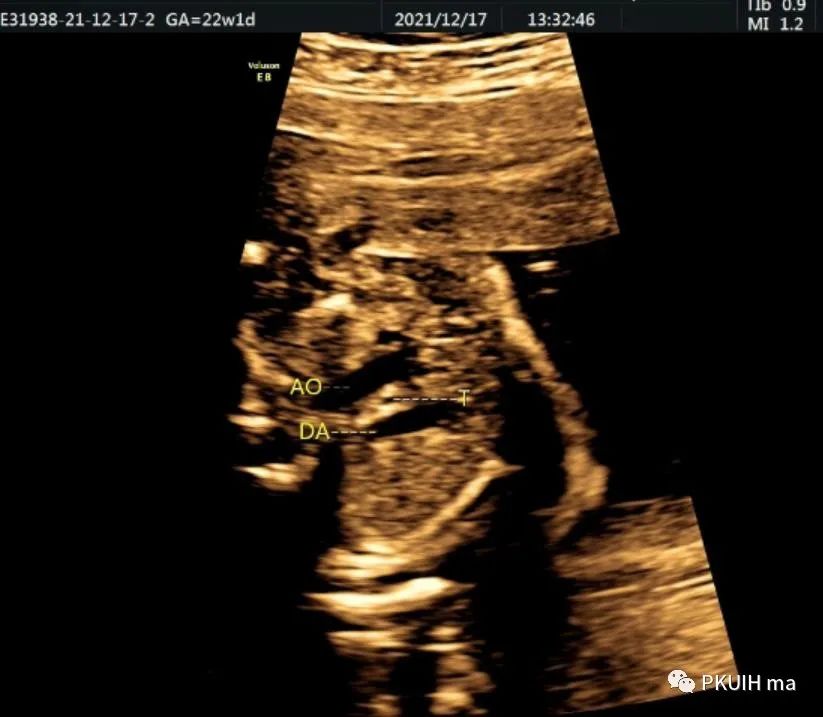

锁骨下动脉观察一般在主动脉弓水平横切面观察,显示左右锁骨下动脉像弓箭样向左右肩部走形。对于迷走的锁骨下动脉观察需要在三血管气管切面和主动脉冠状切面观察。右锁骨下动脉迷走在三血管气管切面可见一血管于主动脉弓降部发出自脊柱前方气管后方向右肩走行,在主动脉冠状切面显示主动脉弓降部见一血管迂曲向右肩部走行,频谱显示为动脉频谱。右锁骨下动脉迷走在三血管气管切面要和左无名静脉鉴别,左无名静脉汇入上腔静脉,频谱为静脉频谱,同时右锁骨下动脉也要和走形于气管后方汇入上腔静脉的奇静脉相鉴别,血流频谱有助于两者鉴别。

脊柱前方一红色血管为迷走的右锁骨下动脉,频谱为动脉频谱

冠状切面显示右锁骨下动脉起于主动脉弓降部(ARSA:迷走的右锁骨下动脉,LSA:左锁骨下动脉)